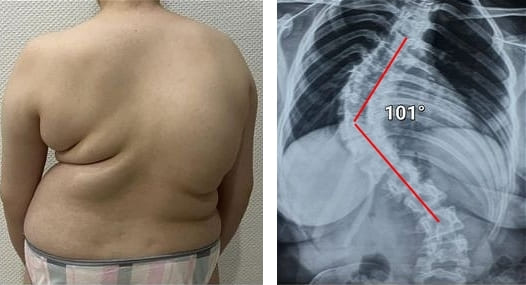

Mire estas fotografías. Esto es lo que les sucedió a todos los que ignoraron los síntomas. Hoy, estas personas están completamente sin esperanza, y muchos de ellos no tienen a quién acudir en busca de ayuda. ¿Realmente, quiere un destino así?

Mujer de 52 años. Desplazamiento y deformación severa del disco intervertebral, compresión de los nervios y daño a la médula espinal.

"Joroba de viuda" — deformación de las vértebras y dolor crónico, insoportable, que se intensifica cada día.